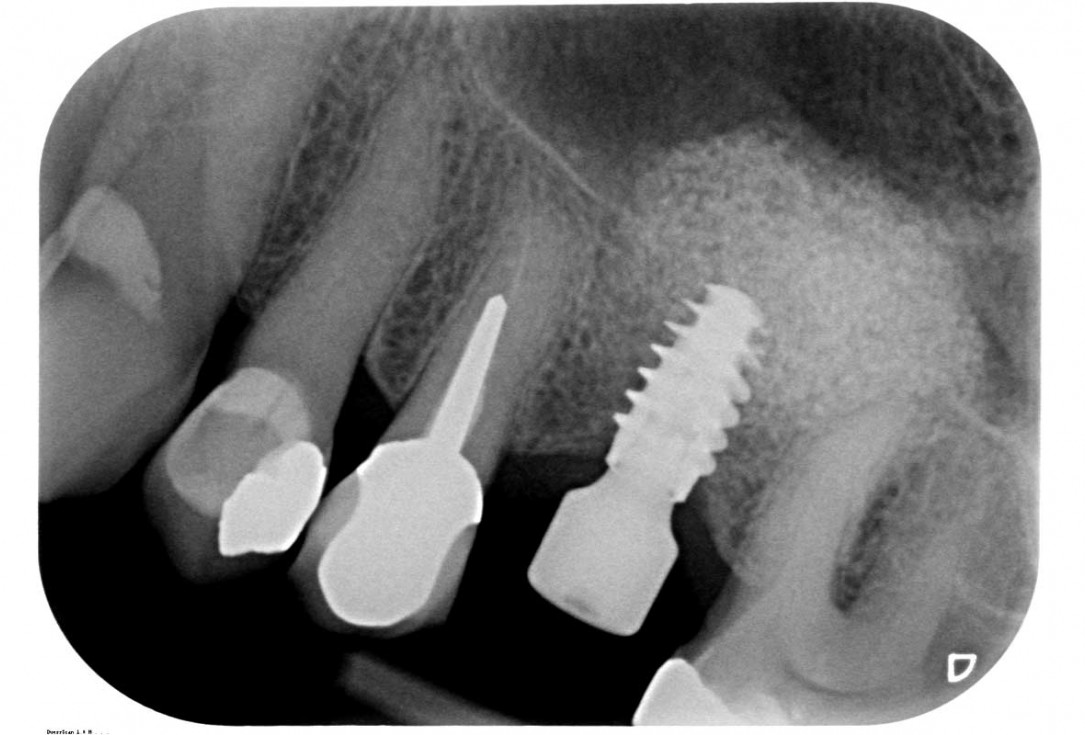

29/35 - X-ray control after the second stageMaxillary sinus cyst removal using the Crocodile Technique and subsequent lateral sinus lift - Dres. C. Scognamiglio and A. Perucchi